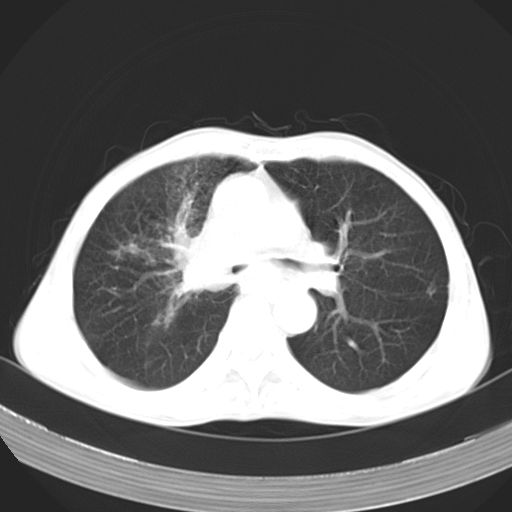

以下是引用苯小孩在2007-5-24 12:47:00的发言:[br]右侧肺门处不均匀密度软组织块影,远端肺组织见斑片模糊影,纵隔内淋巴结明显肿大,边界不清.<纵隔窗第12层面支气管内似见软组织结节>[br]考虑:1、右侧中央性肺癌并阻塞性肺炎并纵隔淋巴结转移可能性大.建议强化或纤支镜进一步检查.[br]2、隆突下淋巴结肿大/食道病变?请做鉴别检查.

以下是引用zhangzhongshou在2007-5-24 12:55:00的发言:[br]1、右肺中叶中心型肺癌并右肺门、隆突下、纵隔淋巴结转移。右肺中叶阻塞性肺炎。

以下是引用jw-830在2007-5-24 15:24:00的发言:[br][br] [br] 考虑右肺中央型肺癌并阻塞性炎症,右肺门及纵隔淋巴结转移。 [br] [br][br]